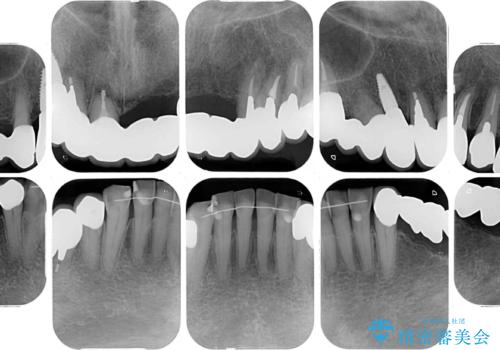

処置を予定していた歯を仮歯に変えた時点で、下顎前歯の部分矯正を行うかどうかを尋ねたところ、折角なので行いたいと言うことでしたので、矯正治療を行うこととしました。

インプラント埋入や根管治療治療など、治癒に一定の期間を要する処置の合間に矯正治療を行うことで、効率的に治療を進めて行くことができました。